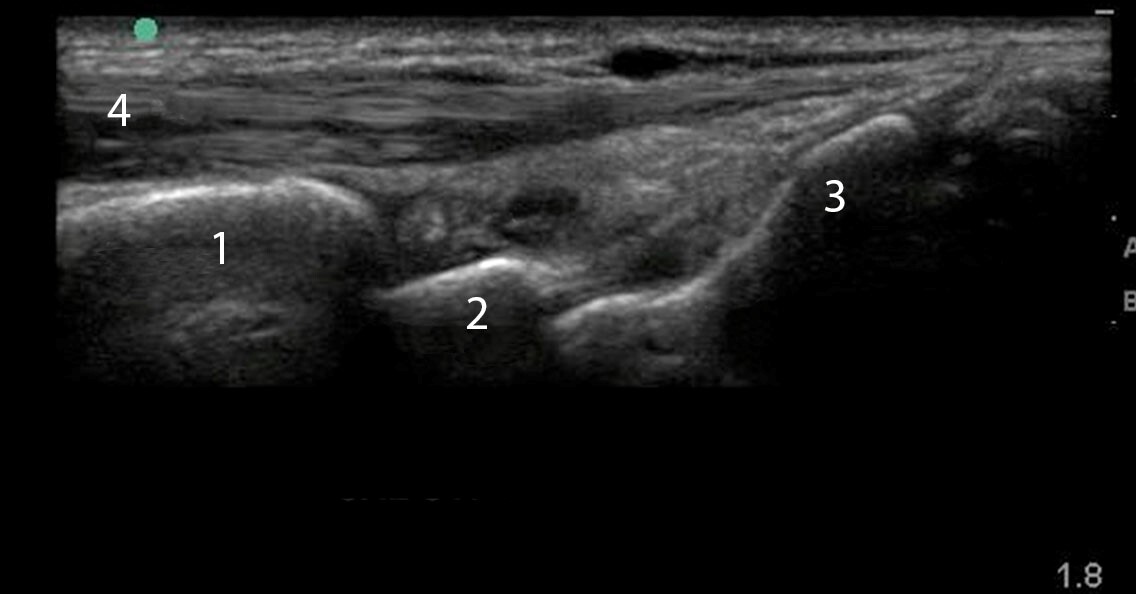

Wrist Dorsal Synovitis Longitudinal Image

Radius

Lunate

Capitate

Extensor Tendon